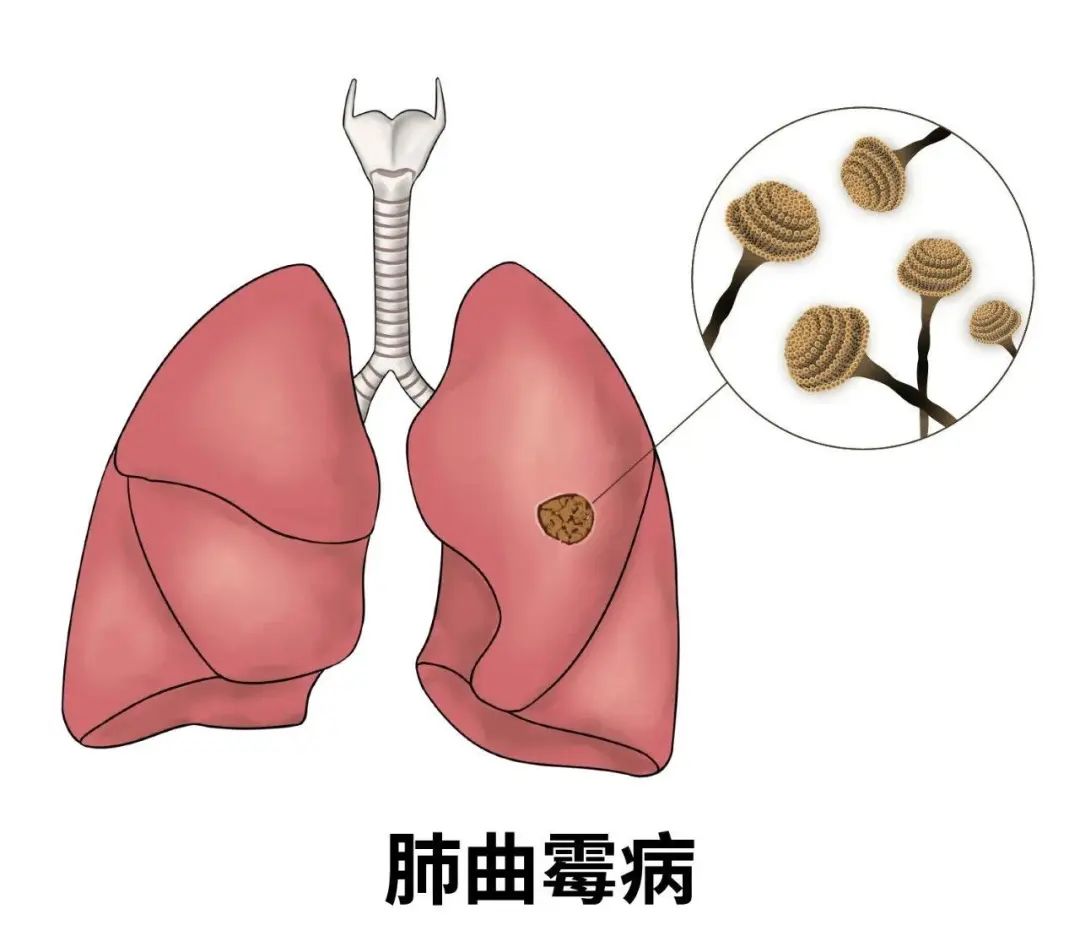

曲霉菌是如何长进肺里的?

曲霉菌是一种真菌,被世界卫生组织列为一等致癌物质,其毒性是砒霜的68倍。它广泛存在于自然界中,主要以枯死植物、动物排泄物及尸体为营养源。

人体免疫系统受到攻击或免疫力较弱时,曲霉菌就可能进入肺部,引起肺曲霉病。